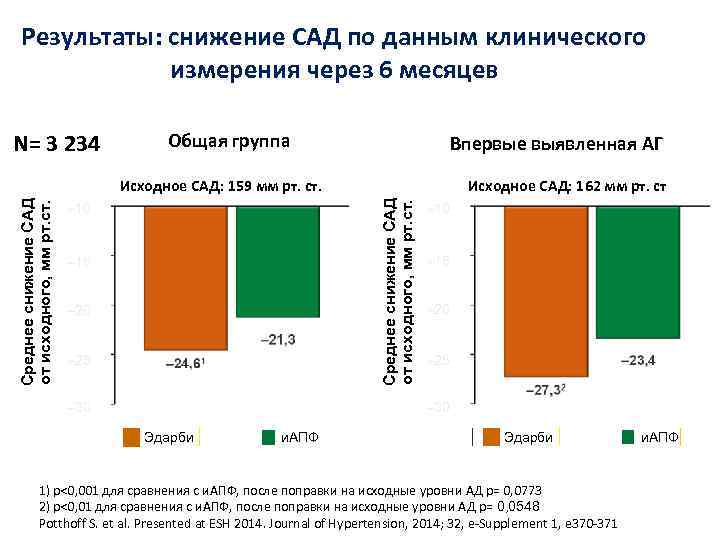

Результаты: снижение САД по данным клинического измерения через 6 месяцев N= 3 234 Общая группа Впервые выявленная АГ Исходное САД: 162 мм рт. ст Среднее снижение САД от исходного, мм рт. ст. Исходное САД: 159 мм рт. ст. – 10 – 15 – 20 – 25 – 30 Эдарби и. АПФ Эдарби 1) p<0, 001 для сравнения с и. АПФ, после поправки на исходные уровни АД р= 0, 0773 2) p<0, 01 для сравнения с и. АПФ, после поправки на исходные уровни АД р= 0, 0548 Potthoff S. et al. Presented at ESH 2014. Journal of Hypertension, 2014; 32, e-Supplement 1, e 370 -371 и. АПФ

Результаты: снижение САД по данным клинического измерения через 6 месяцев N= 3 234 Общая группа Впервые выявленная АГ Исходное САД: 162 мм рт. ст Среднее снижение САД от исходного, мм рт. ст. Исходное САД: 159 мм рт. ст. – 10 – 15 – 20 – 25 – 30 Эдарби и. АПФ Эдарби 1) p<0, 001 для сравнения с и. АПФ, после поправки на исходные уровни АД р= 0, 0773 2) p<0, 01 для сравнения с и. АПФ, после поправки на исходные уровни АД р= 0, 0548 Potthoff S. et al. Presented at ESH 2014. Journal of Hypertension, 2014; 32, e-Supplement 1, e 370 -371 и. АПФ